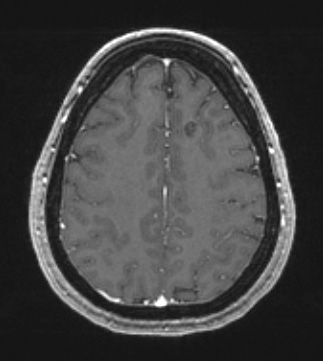

30A3 Cavernous angioma (Case 30) T1W - Copy

30A2,3 The lesion shown in T1-weighted scan with contrast fails to enhance.